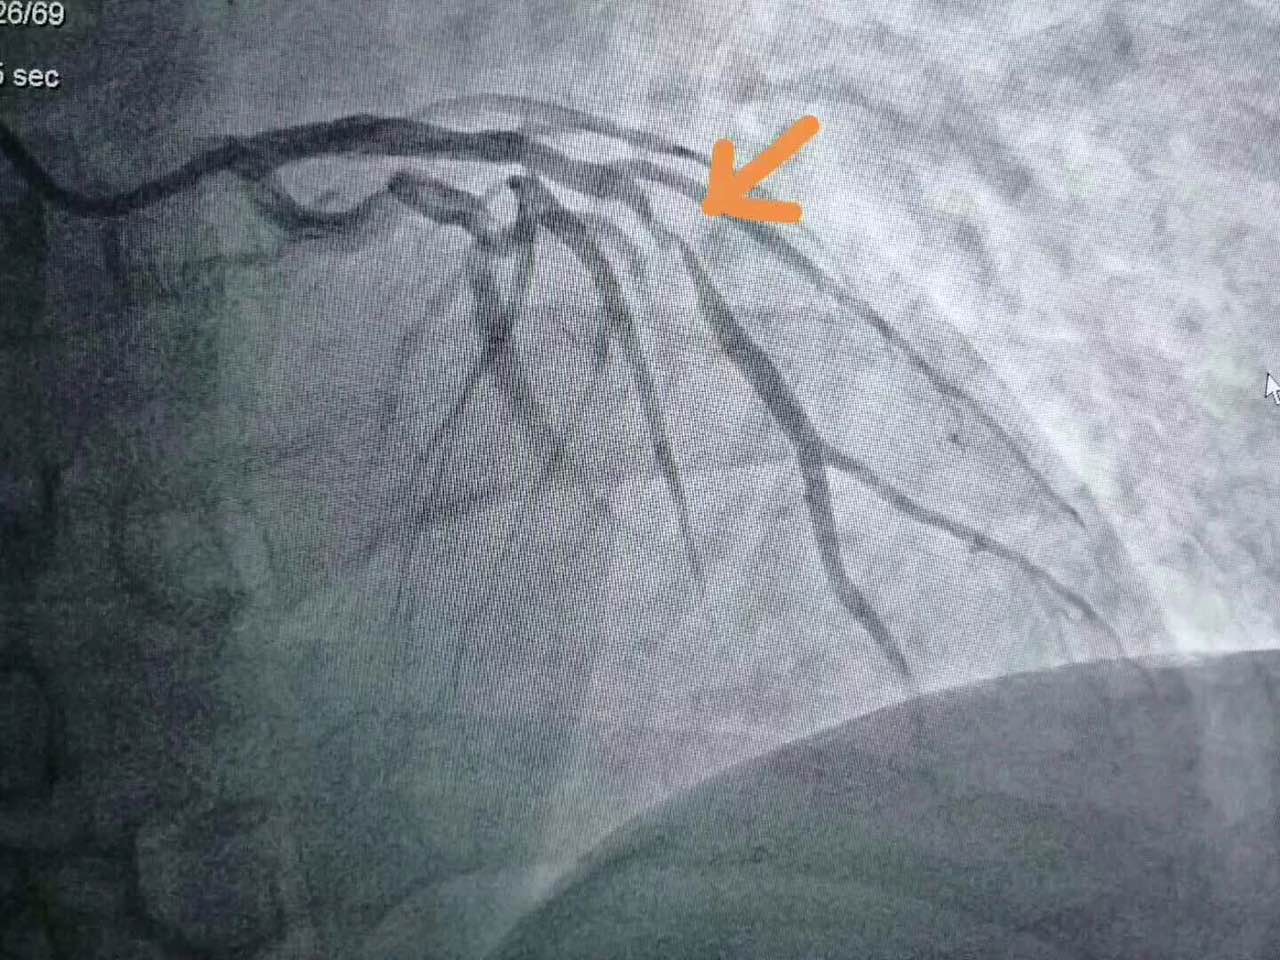

据造影显示,刘先生冠脉三支病变,其中左前降支及左回旋支重度病变,右冠中重度病变,属于冠状动脉粥样硬化性心脏病。

在刘先生及家人的共同意愿下,团队立即为进行了左前降支及左回旋支PTCA+左前降支Resolute药物支架1枚植入术和左回旋支Resolute药物支架2枚植入术。手术由浙一医院心血管内科导管室副主任、主任医师尚云鹏主导,介入中心团队配合,历时仅约30分钟。

张清德十分认真地把患者术前术后的造影影像发到多个医患群中,提醒大家——抽烟有害健康,劝君珍惜莫大意!